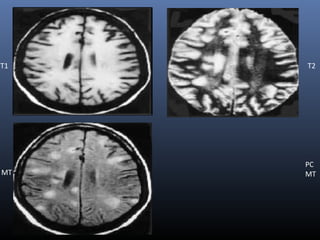

T1 T2

MT

PC

NEUROCYSTICERCOSIS

Findings vary with the stage of disease

 T1-W MT images are also important in demonstrating perilesional gliosis

in treated neurocysticercus lesions

 Gliotic areas show low MTR compared to the gray matter and white

matter. So appear as hyperintense